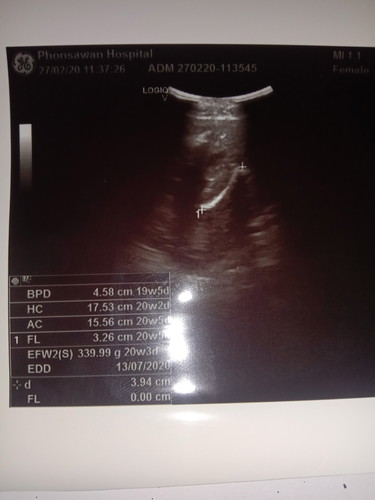

มีใครไปชาวด์ช่วง5เดือนบ้างคะคือน้ำหนักลูก_339.99.Gคือน้ำหนักน้องปกติไหมคะเเม่ๆบ้านไหนรุ้บ้างคะบอกหน่อยค่ะ

ลูกรัก5เดือน

อยู่ในเกณฑ์ปกติค่ะ ตอนเราซาวด์ 19+5 วีค น้ำหนักน้อยกว่านี้นิดหน่อยคุณหมอแจ้งว่าลูกน้ำหนักอยู่ในเกณฑ์ค่ะ

ปกติค่ะ วันนี้ 20 w ไปซาวด์มาเหมือนกันค่ะดูอวัยวะที่สำคัญๆ หมอจะบอกนะคะว่า นน ลูก ขนาดตัว ปกติดีมั้ย